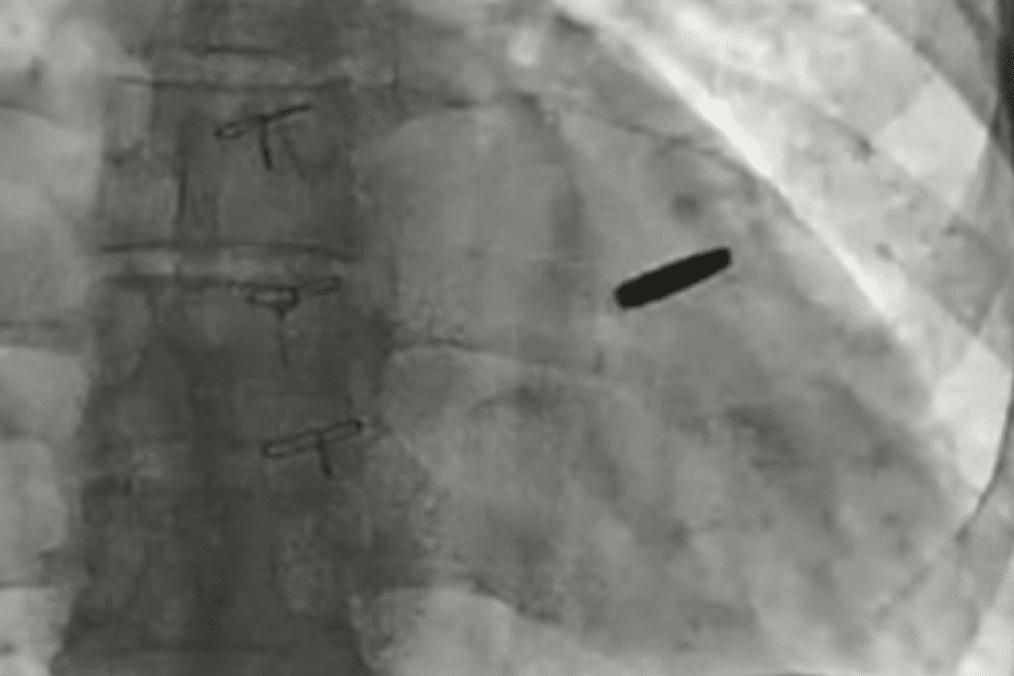

Ukrainian doctors have removed a bullet lodged in the heart of a soldier who defended Mariupol’s Azovstal steel plant and survived three years in Russian captivity, according to Borys Todurov, director of Ukraine’s Heart Institute, on September 19.

Todurov said the bullet miraculously missed vital structures, allowing the fighter to live with it embedded in his heart for three years.

“The bullet has now been removed. The guy got lucky. I think he will live a long and happy life,” Todurov said, holding up the projectile during a press briefing.

He described the soldier as “invincible” and praised his resilience: “Three years in captivity with a bullet in his heart. These people are titans. Unconquerable!!!”

Doctors said the bullet caused no serious damage during the years it remained lodged in the heart.